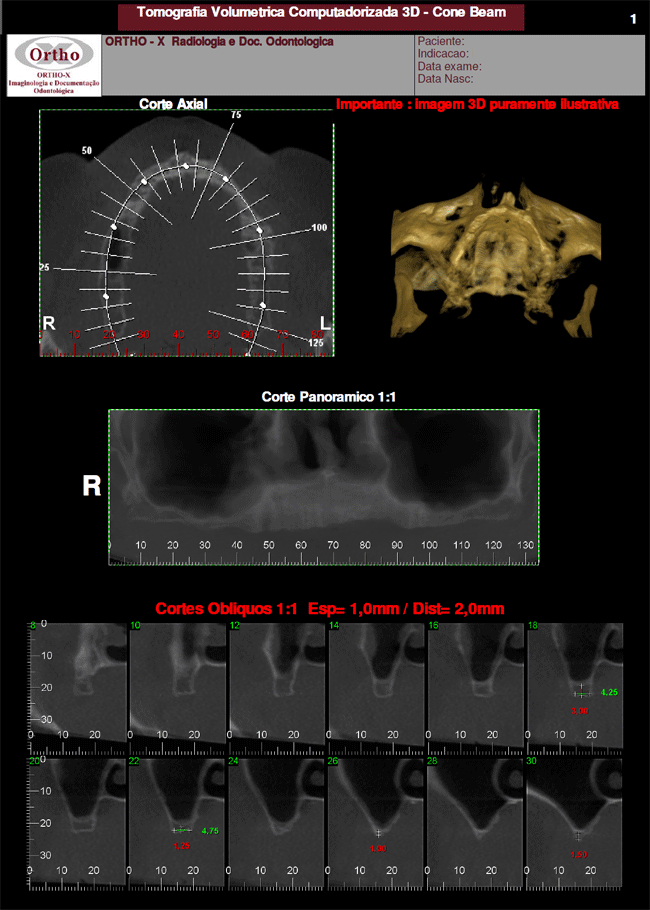

A tomografia CONE BEAM é um exame de alta resolução que é capaz de analisar os dentes e suas estruturas ósseas vizinhas em três dimensões. É permitida a avaliação de mensurações da altura, largura e profundidade das estruturas, o que não é possível com os exames radiográficos convencionais. Estas informações proporcionam mais segurança para os procedimentos, aumentando os índices de sucesso terapêutico.